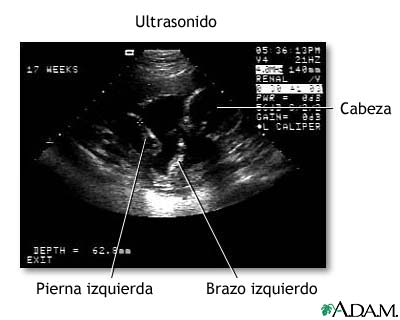

Este ultrasonido para fetos normales se realiza a las 17 semanas de gestación. El desarrollo del cerebro y del sistema nervioso se inicia temprano en el desarrollo fetal. Durante un ultrasonido, el técnico busca, por lo general, la presencia de ventrículos cerebrales. Los ventrículos son espacios en el cerebro que se llenan con líquido. En este ultrasonido inicial, los ventrículos pueden observarse como líneas delgadas que se extienden a través del cráneo y aparecen en la parte superior derecha de la imagen.